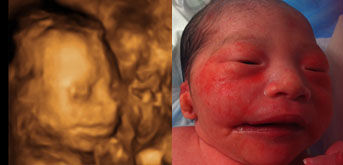

B超是利用超声波探测技术对人体脏器进行检查,没有电离辐射、电磁辐射,相对安全,因此用于对胎儿的结构进行检查就有突出的优势。B超从最早的普通B超,到彩色B超,再到今天的4维彩超。4维超声技术就是采用3维超声图像加上时间维度参数,这项技术能够实时获取三维图像,超越了传统超声的限制。它提供了包括腹部、血管、小器官、产科、妇科、泌尿科、新生儿和儿科等多领域的多方面的应用。尤其在对胎儿的产前筛查方面更是立下了汗马功劳。

现代的产科,产科医生再有经验,也不能看到宫内胎儿的形态、脏器,已经不能离开B超检查了,七个月之前的各项检查都与筛查胎儿畸形有关,11-13周时胎儿颈部皮肤透明层是筛查21-三体的重要指标;22周左右时胎儿畸形的排查;24-28周时胎儿先天性心脏病的检查。七个月之后30-32周时胎儿畸形的补漏筛查;37周时胎儿宫内安危的筛查(包括脐带缠绕、羊水多少、胎盘功能、脐血流比值的测定、生物物理评分等)。因此产科B超在提高出生人口质量、维护母婴安全方面起到了令世人瞩目的作用。文/赵天卫